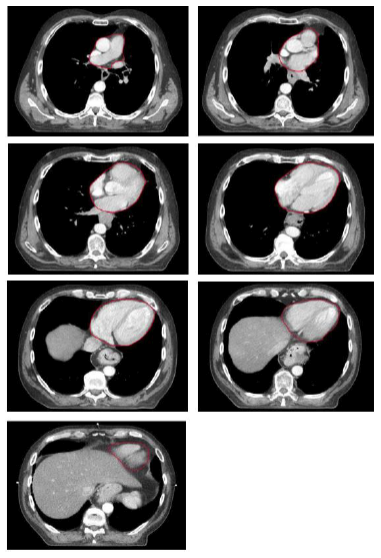

Contouring atlas: heart

Outlining of the heart

Superiorly, the heart starts just inferior to the left pulmonary artery. For simplification, a round structure to include the great vessels is contoured. Inferiorly, the heart blends with the diaphragm. Since cardiac vessels run in the fatty tissue within the pericardium, they should be included in the contours, even if there is no heart muscle visible in that area.